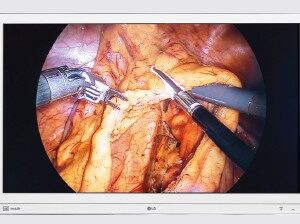

SKU: UP-27MD - Monitores LG, Monitores Médicos

Monitor Quirúrgico LG – 27HK510S

- Sector: Ideal para entornos de cirugía, endoscopia y laparoscopia.

- Excepcional calidad y precisión

- Resolución de 2MP (1920 x 1080) pixeles

- Calibración por hardware

- True Color Pro

- Diseñado para salas de operaciones

- Confort visual de larga duración

- Ancho: 654,4 mm.

- Alto: 412,90 mm.

- Fondo: 62,20 mm

- Peso: 7,70 Kg.

- Alimentación 100-240 VAC

- Seguridad: IEC60601-1 / IEC60601 -1 – 2